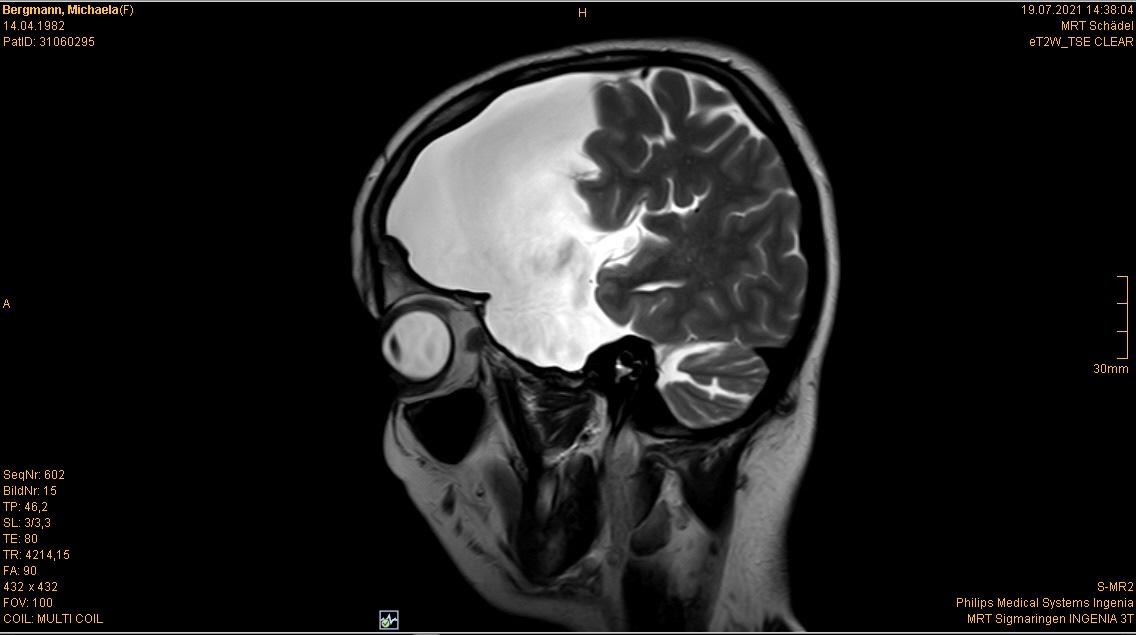

Im Juli stand ja auch noch mein jährliches Kopf MRT an. Ist ja schon quasi „same procedure as every year“. Es gab nichts überraschend Neues oder so. Wenn man es optimistisch sieht kann man sagen: Unverändert. Wenn man es realistisch sieht: gleich beschissen wie vorher

Für alle, die sich neu hier auf meinem Blog tummeln und schon an der ein oder anderen Stelle von meinem „Untermieter“ gelesen haben, sei er hier noch einmal mit den aktuellsten Bildern „vorgestellt“

Die Bilder sind also die aktuellsten vom 19.07.2021. Ja ich weiß, der ist ja riesig, ja ich weiß, dass das ja echt shit ist usw. usw. Aber das weiß ich nun schon seit dreizehn Jahren und ich habe mich damit arrangiert und abgefunden. Womit wir zum nächsten Gedankenthema kommen.

Es ist für mich ja nicht mehr schockierend, wenn ich die Bilder sehen, denn ich weiß ja was mich erwartet. Aber für den ein oder anderen Außenstehenden oder mich noch nicht kennenden Mitarbeiter in der Radiologie im Krankenhaus ist das doch schon immer wieder was Besonderes. Und als ich dieses Mal so den MRT Gang entlang schritt und herein gerufen wurde, wusste die eine Mitarbeiterin, dass ich nun schon zum 37sten Mal das ganze Prozedere über mich ergehen lasse und sagte dementsprechend nicht mehr viel zu mir (bzgl. alles mit Metall muss ausgezogen werden vorher, dann wird der Kopf mit einer Art Kopfkäfig fixiert, dass man ihn während der Aufnahmen nicht bewegt usw.). Es läuft alles wie eine Art Routine und im stillen Einvernehmen zwischen uns ab. Der andere Mitarbeiter der da war, war sichtlich irritiert. Und wollte mir zuvorkommen und mich aufklären, wusste aber auch nicht ob er das, weil seine Kollegin (wohl auch seine Vorgesetzte) schwieg, irgendwie nicht richtig wäre usw. Während ich dann immer so im MRT liege und die Bilder gemacht werden (das dauert dann immer gut so zwanzig Minuten) gehen mir auch meist zig Sachen durch den Kopf. Ehrlich gesagt keinerlei Gedanken bzgl. des MRTs selbst, sondern eher bzgl. dem was seit meinem letzten Besuch hier mal wieder alles so los war und passierte.